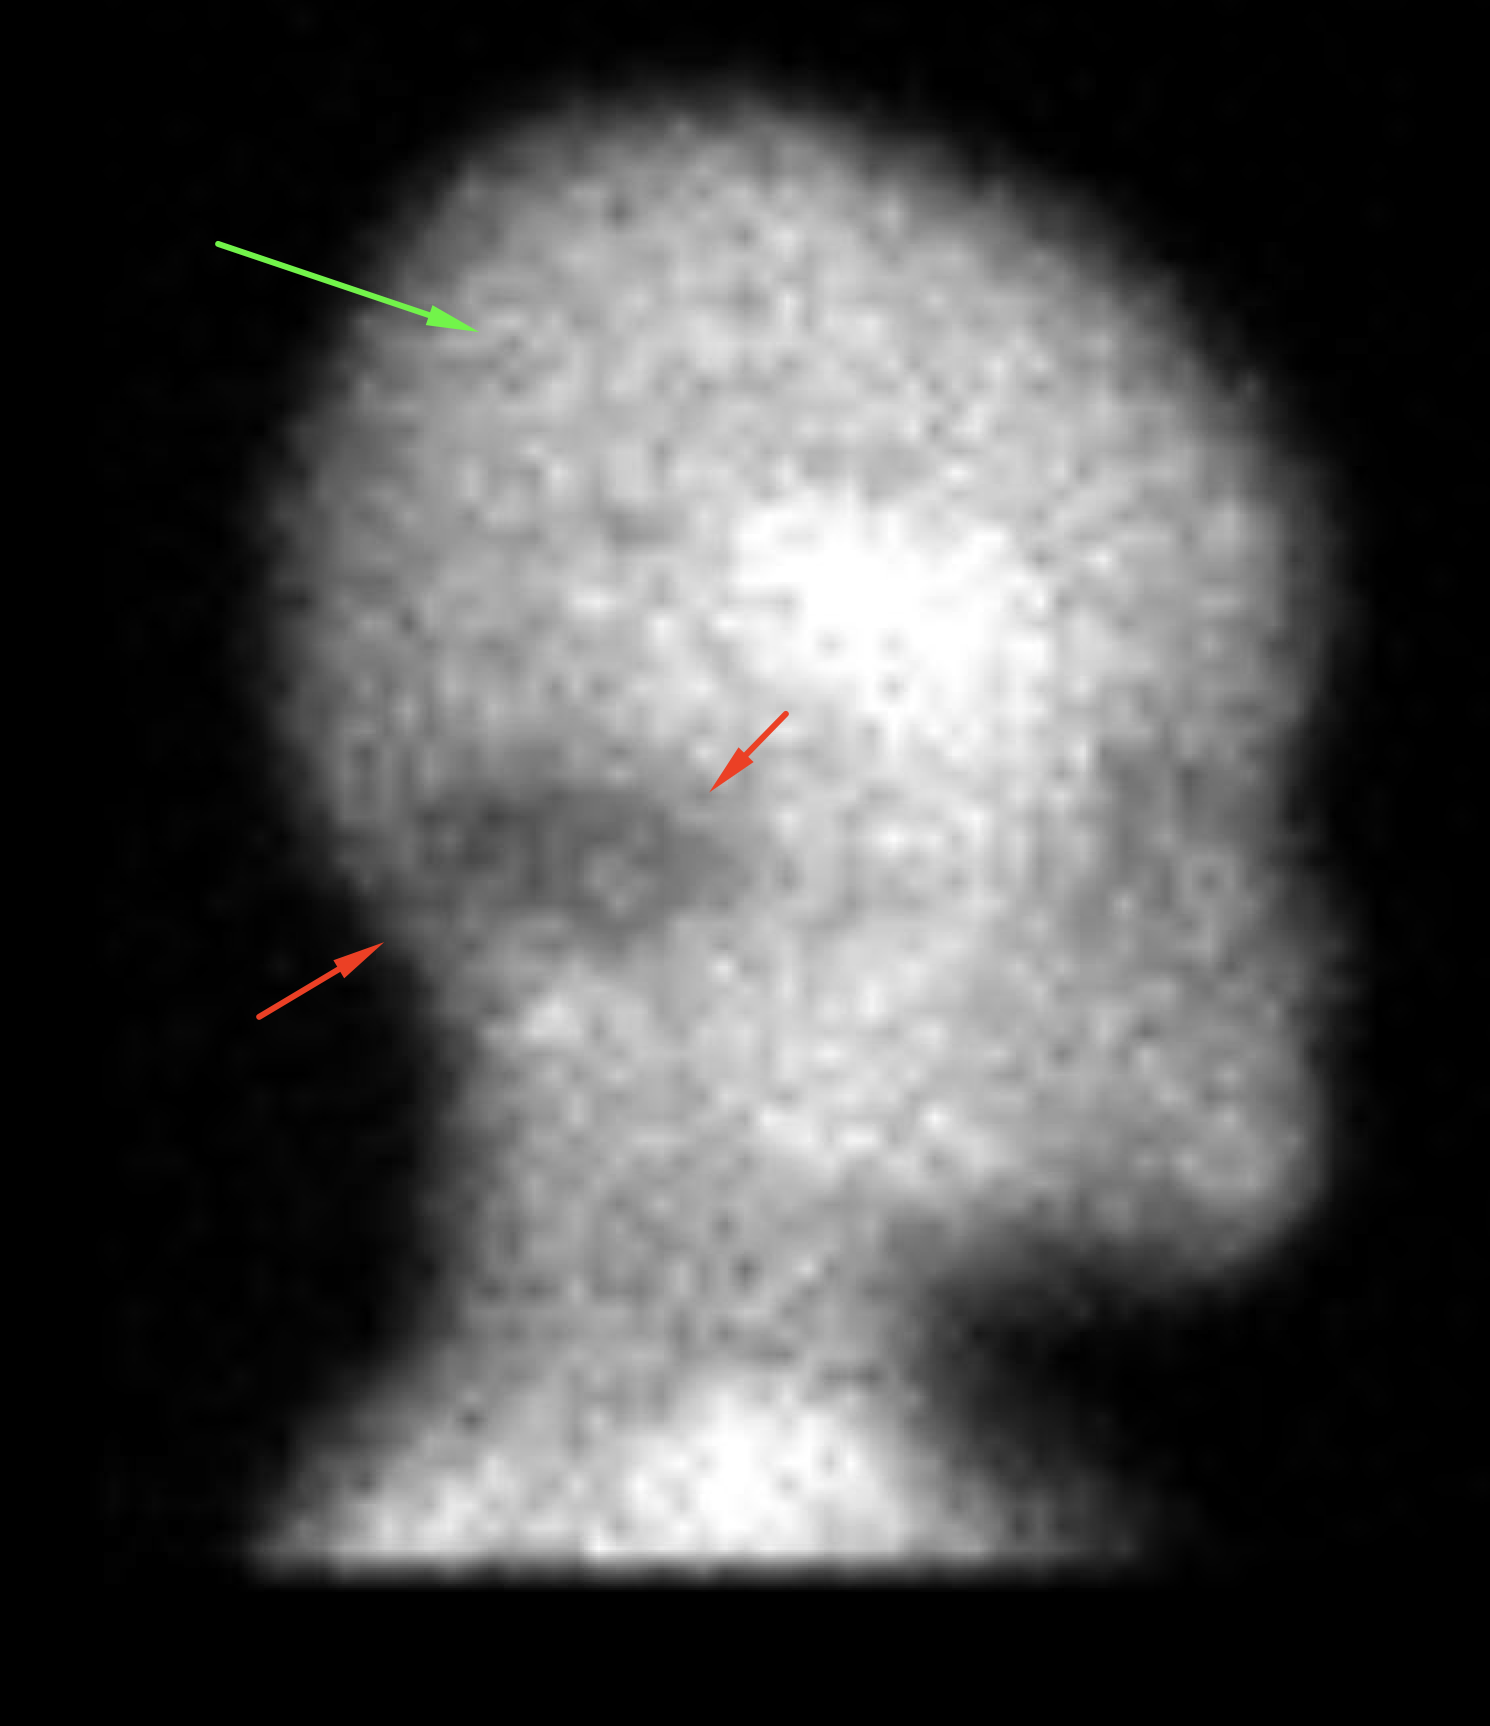

Indication: Cardiac arrest

Radiotracer: Tc99m ECD (ethyl cysteinate dimer)

Sample ReportFindings not consistent with brain death as there is cerebral blood flow present.

Photopenia of the posterior fossa which may represent decreased or absent cerebellar blood flow. Diagnostic angiogram may further evaluate if it will affect patient management.